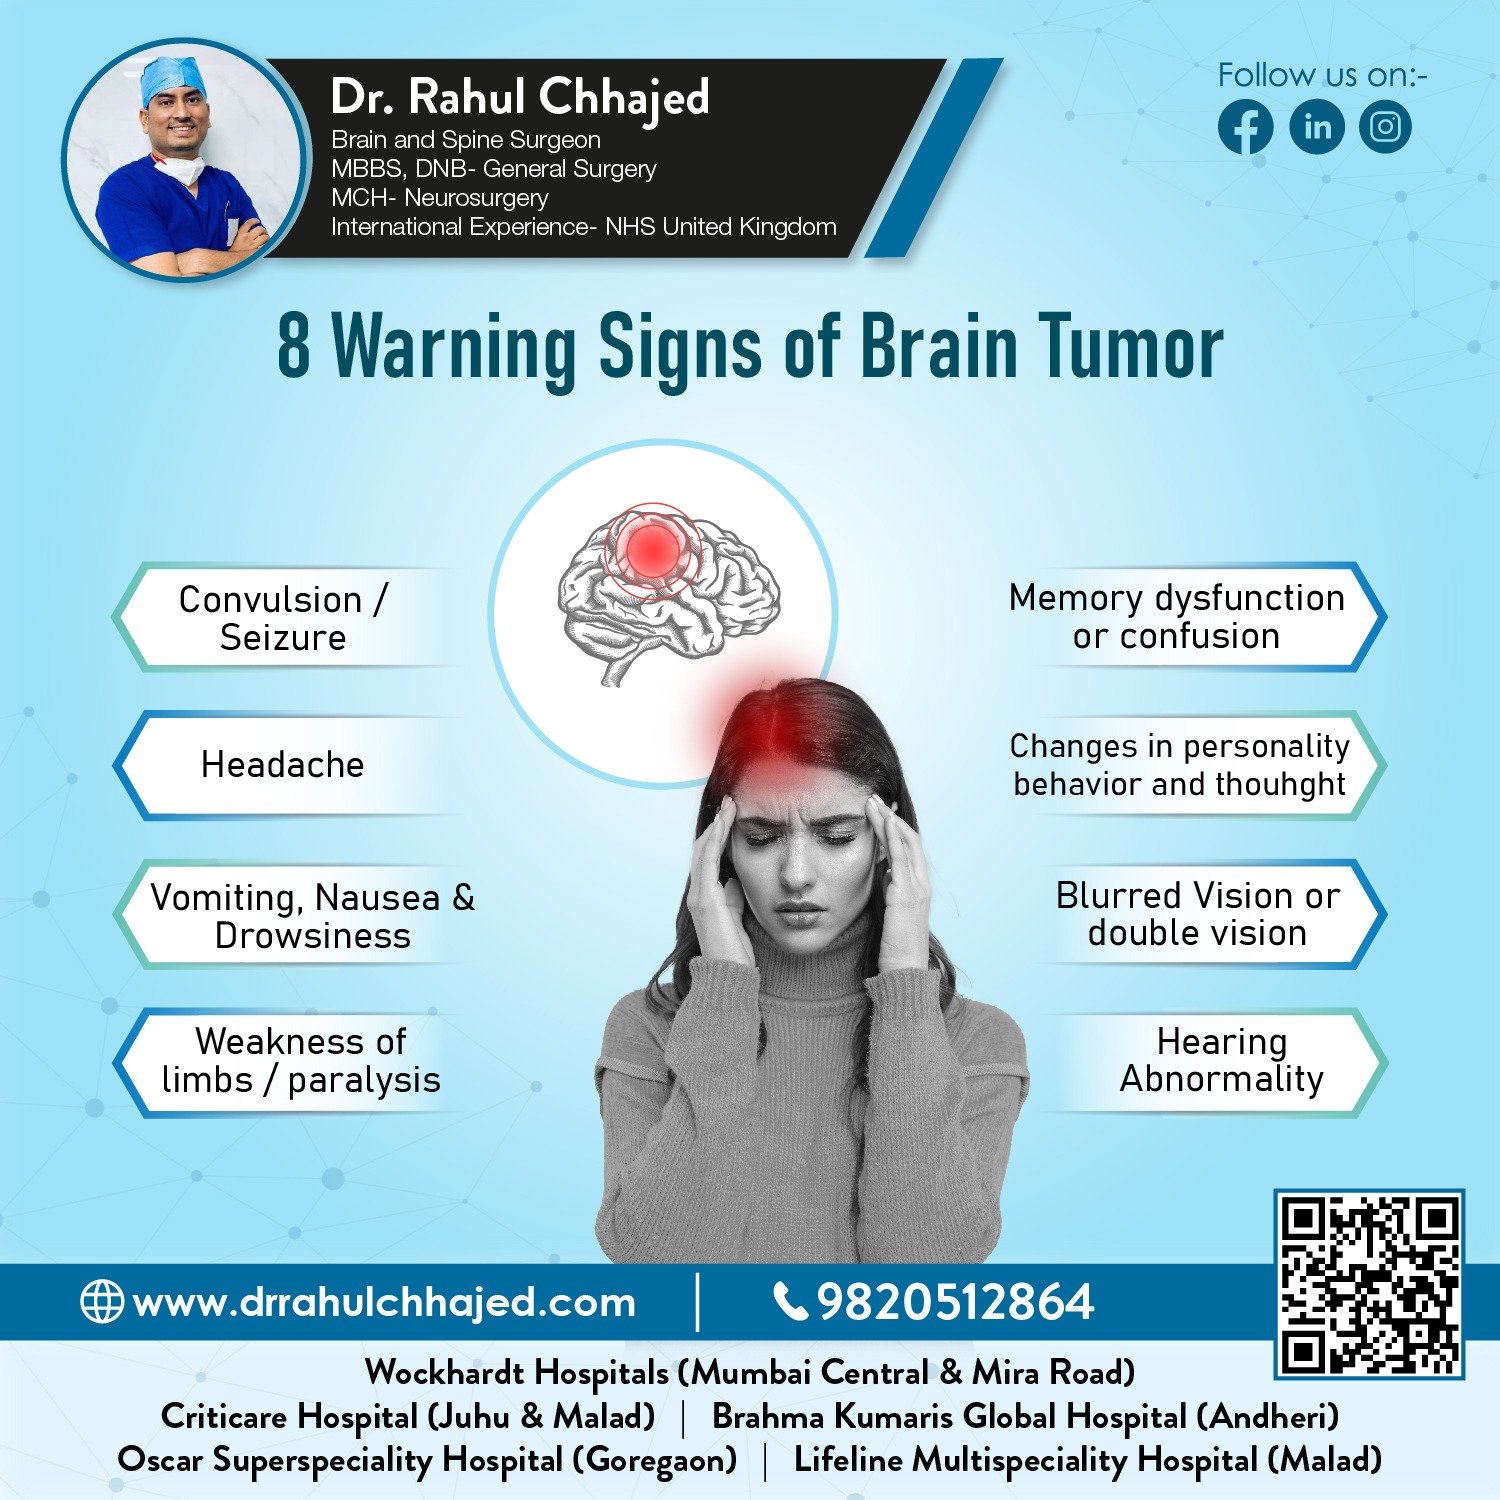

Brain Tumors

Dr. Rahul offers personalized treatment plans for brain tumor patients, taking into account each patient's unique medical history and specific needs. Treatment options may include surgery, radiation therapy, chemotherapy, and targeted therapies.